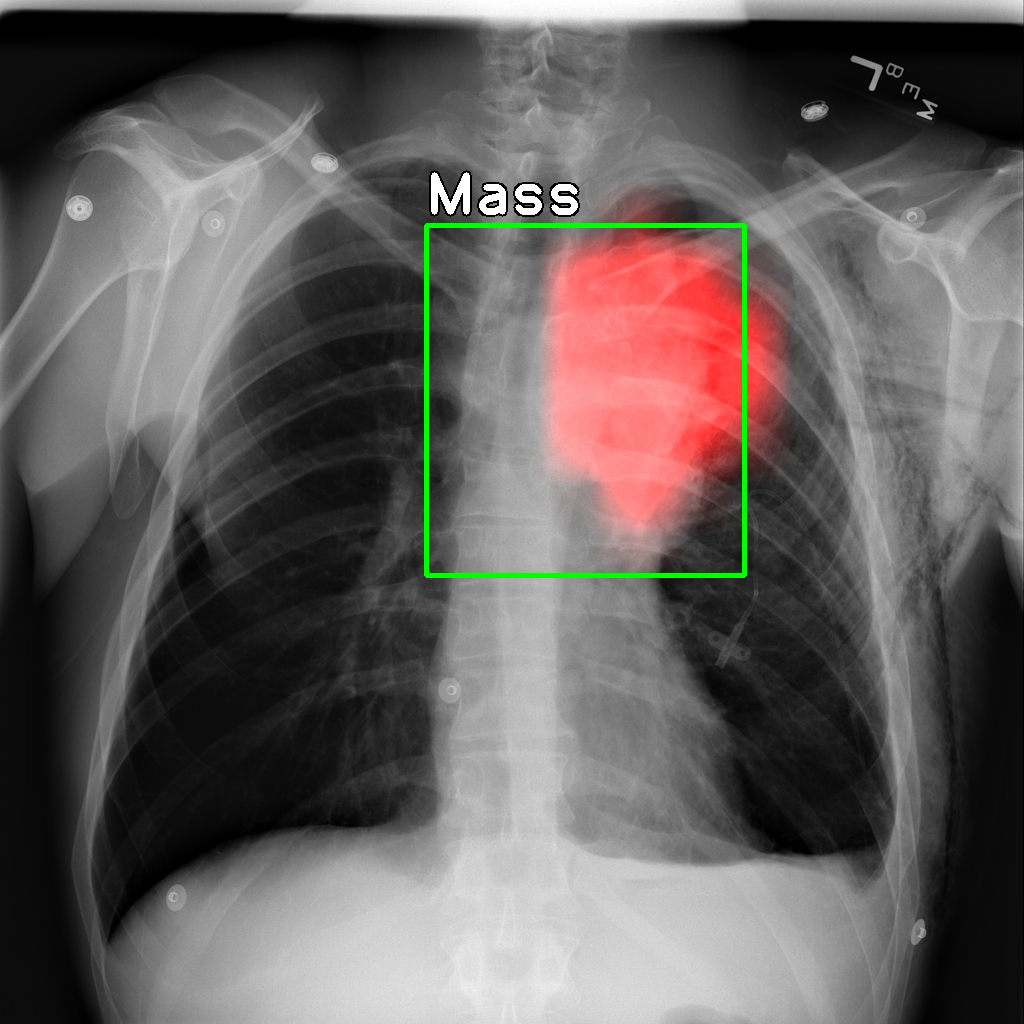

We note that the IoR data is fairly similar to the IoU data, and most of the observations above hold in this case as well. Qualitative examples of the localizations derived are shown in Figure 1.